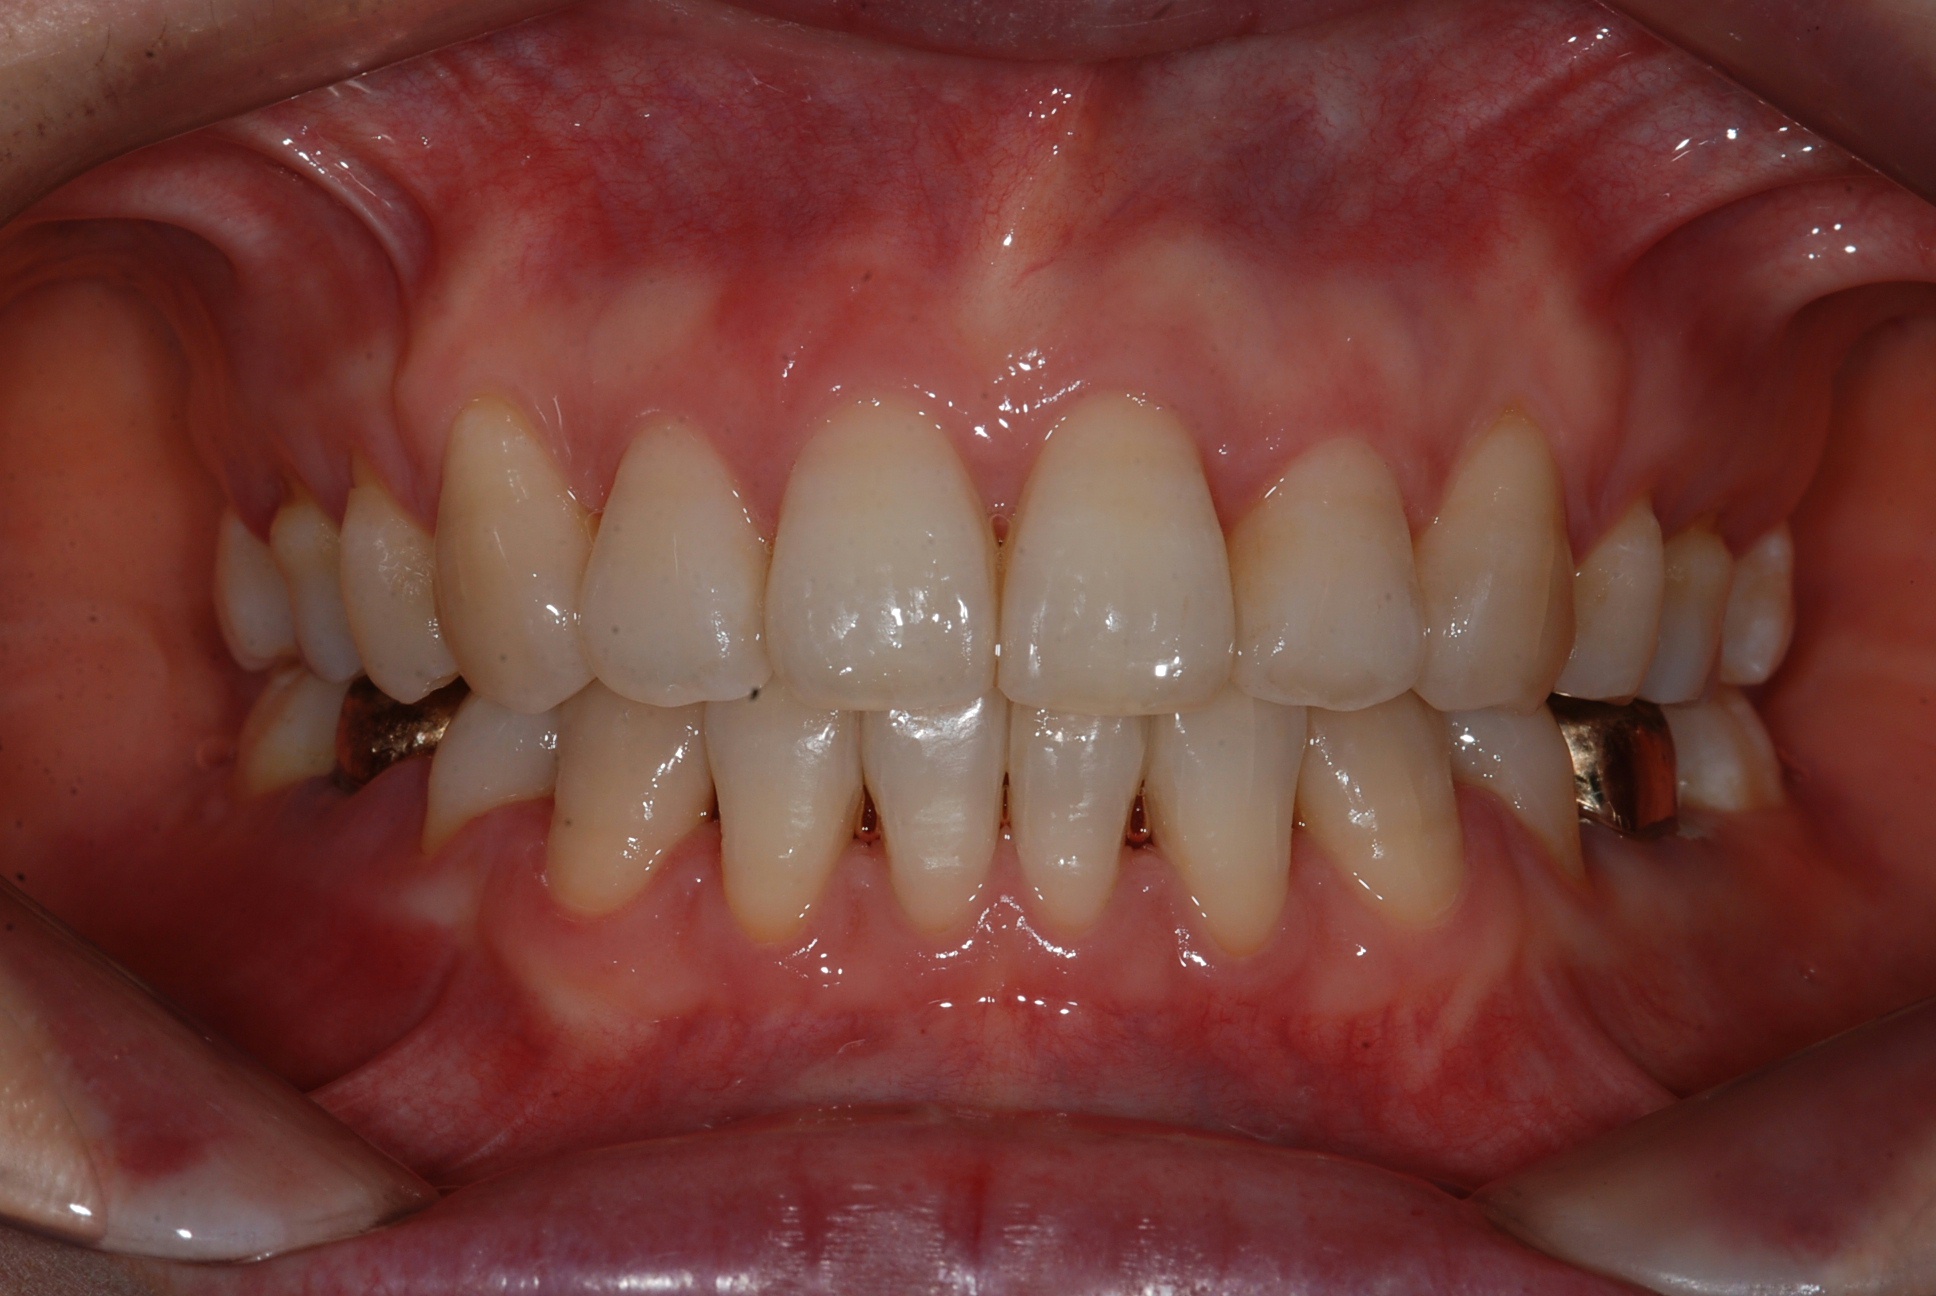

치료 전 사진입니다.